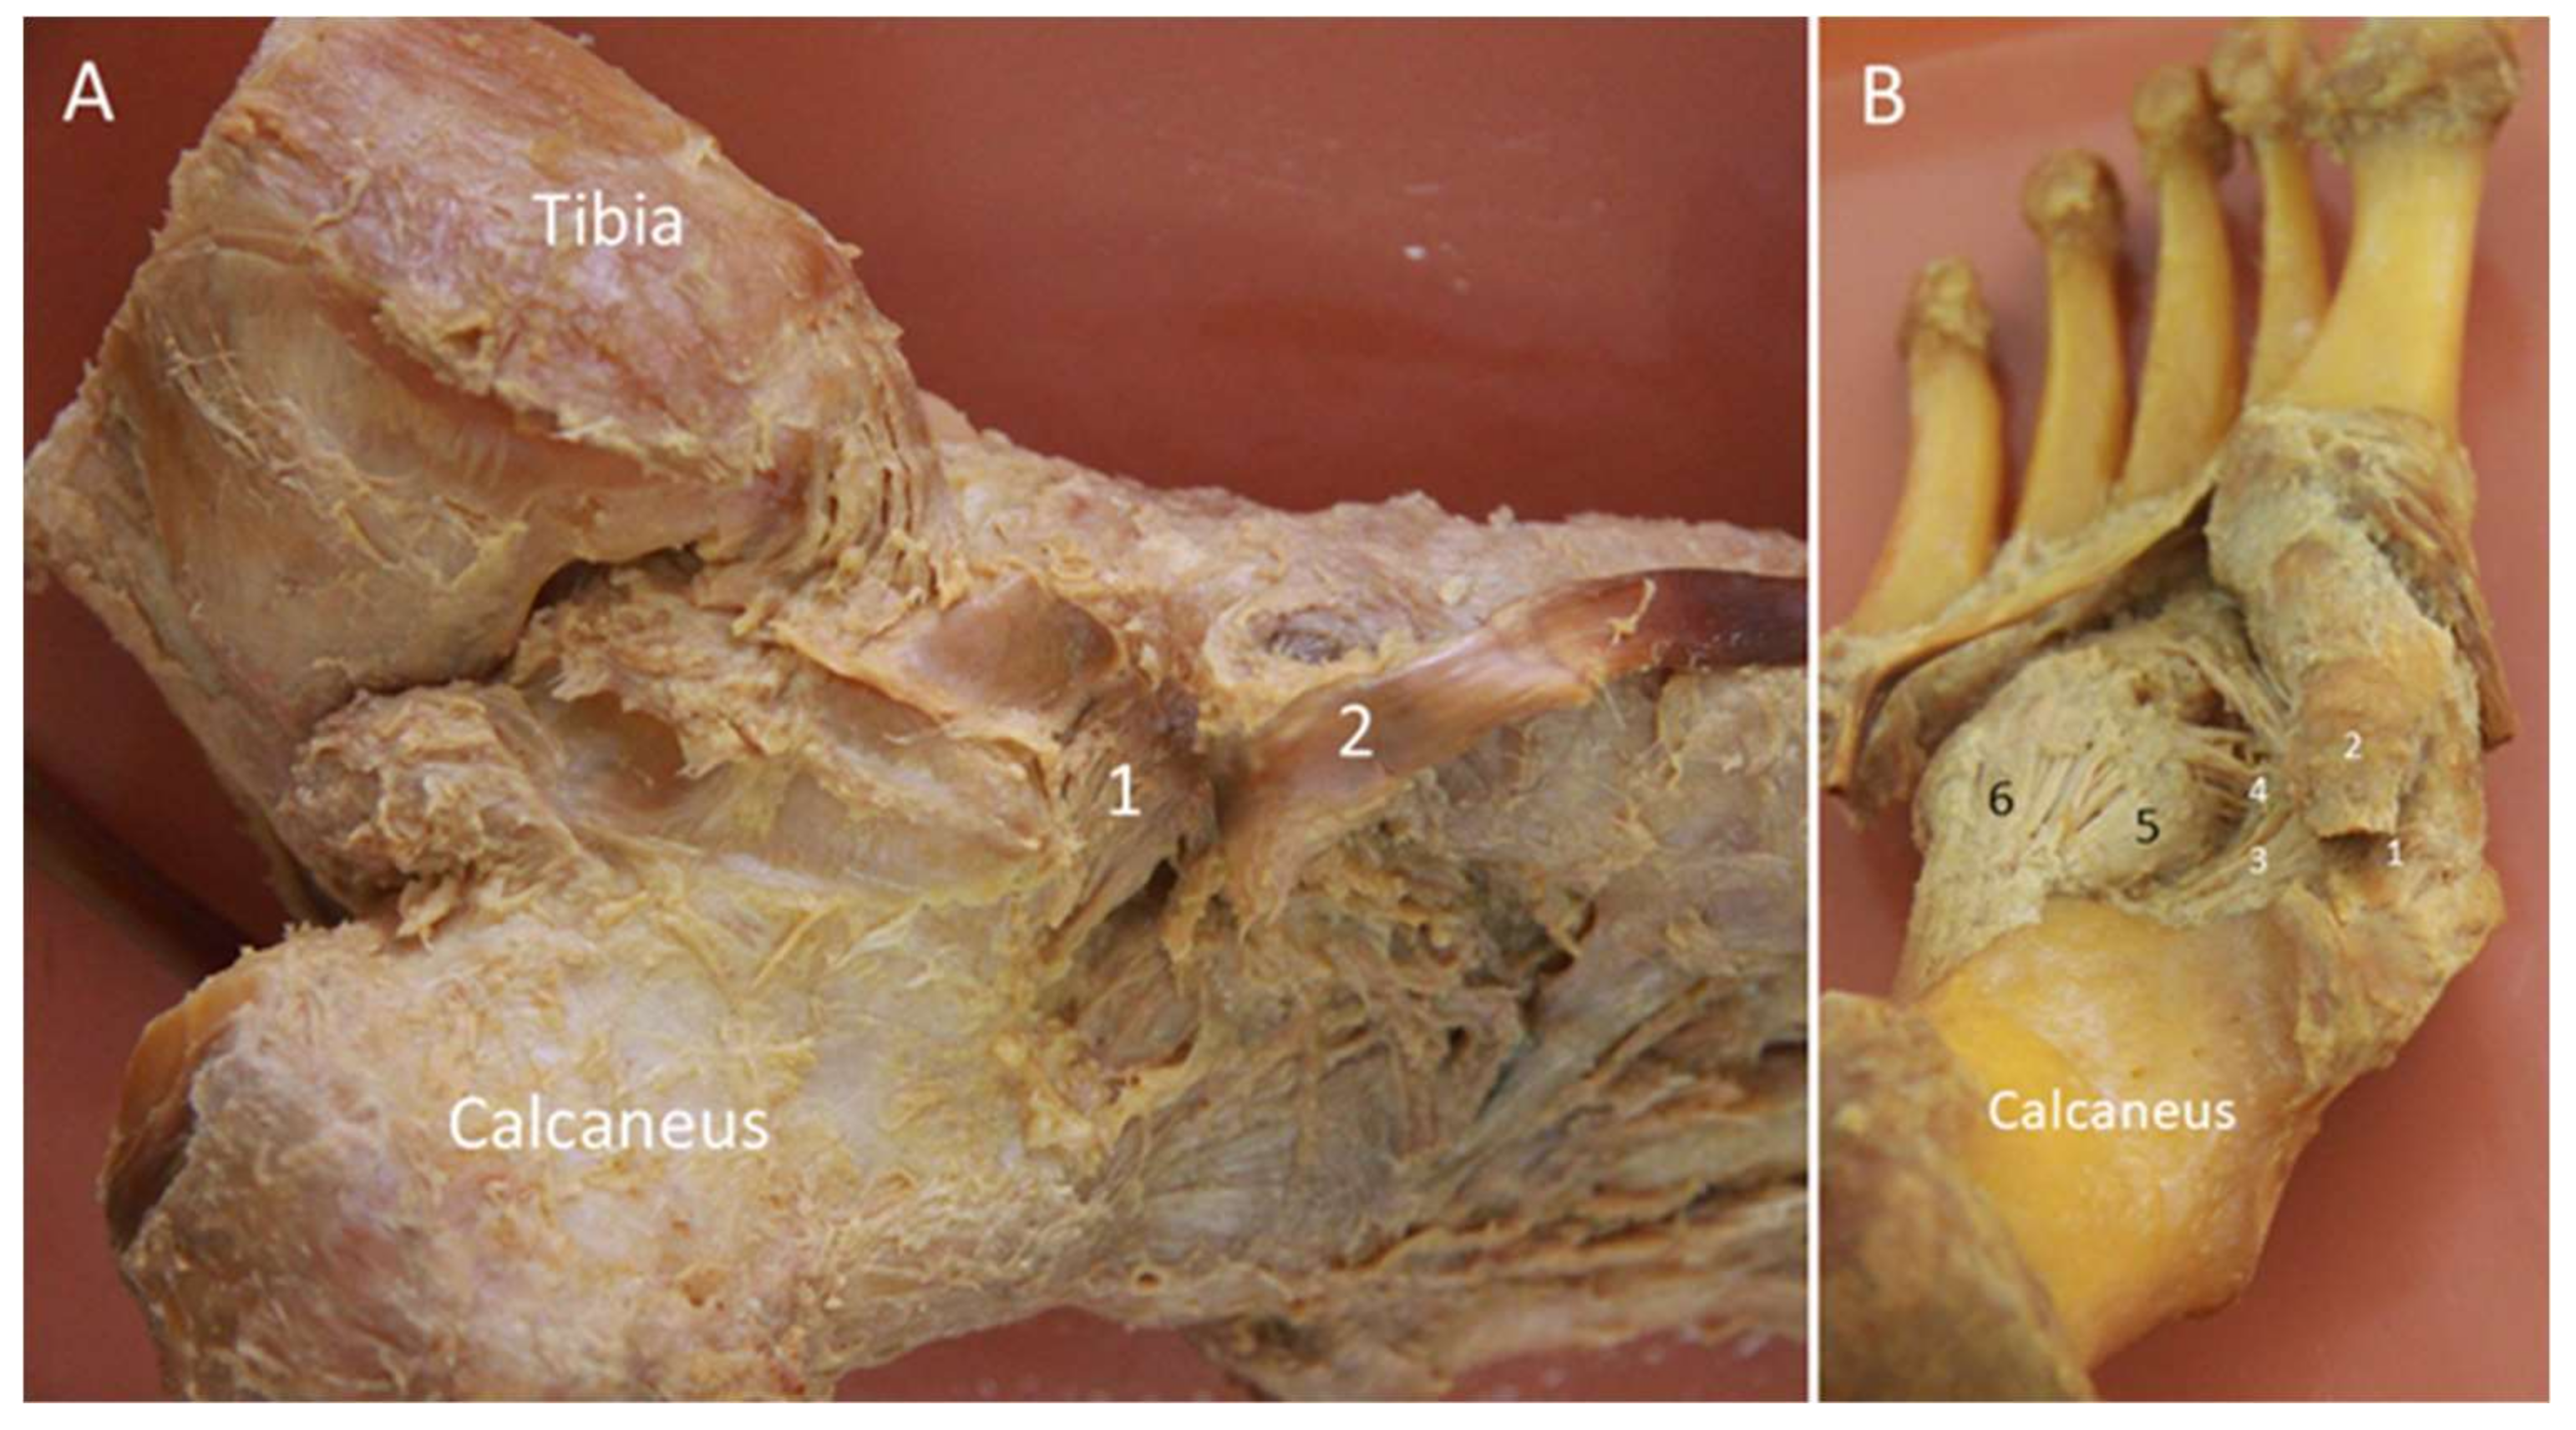

2.7. Deltoid Ligament

2.7.1. Anatomy

2.7.2. Scanning Technique

2.7.3. Clinical Relevance